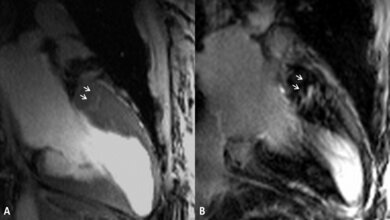

Pragathi Gurumurthy, Doktorandin aus Indien, wurde mit dem wichtigsten Posterpreis der Tagung, dem „Magna Cum Laude Award“, für ihre Arbeit über Messungen der Strömungsverhältnisse in einem Modell der Luftwege von Patienten ausgezeichnet, die am Schlafapnoe-Syndrom leiden. Ihr Beitrag „Study of fluid flow patterns in a human pharynx phantom using phase contrast-MRI“ berichtet über die bei diesem verhältnismäßig häufigen Syndrom auftretenden Atemstillstände, die zu einer Reihe von negativen gesundheitlichen Folgen wie Bluthochdruck, Herzinfarkt und selbst Schlaganfall führen können.

Numerische Simulationsrechnungen zu den Strömungsverhältnissen

Wenn die Atemstillstände im Schlaf nicht durch den durch eine Atemmaske hergestellten permanenten leichten Überdruck beseitigt werden können, muss in manchen Fällen die Geometrie der oberen Atemwege operativ verändert werden. Die Art der Veränderung muss individuell geplant werden. Vorherzusagen, wie sich dabei die Strömungsverhältnisse verändern, ist aber immer noch schwierig und deshalb Gegenstand aktueller Forschungen. In dem Kongressbeitrag wurden numerische Simulationsrechnungen zu den Strömungsverhältnissen mit Hilfe von kernspintomographischen Messungen an einem im 3D-Drucker entstandenen Modell validiert.